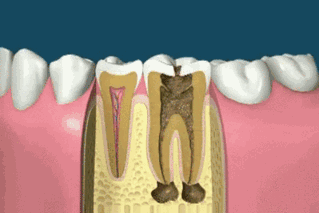

Commençons par le commencement.La structure d'une dent, de l'extérieur à l'intérieur, se compose de trois couches principales :

- l'émail dentaireLa couche externe du tissu dentaire qui recouvre la dent, deuxième après le diamant en termes de dureté, sans qu'aucune douleur ne soit ressentie.

- dentineLa substance qui forme le corps principal de la dent, située dans les couches internes de l'émail et de l'os, et qui n'est pas aussi dure que l'émail.

- pulpe dentaireLe nerf médullaire : Partie la plus interne de la dent, constituée de vaisseaux sanguins et de nerfs, le nerf médullaire est particulièrement sensible aux stimuli externes et peut produire une douleur insupportable et intense.

C'est à partir de ces trois couches de la structure de la dentine que les vers de la dent envahissent, étape par étape, de l'extérieur vers l'intérieur.Il existe plusieurs étapes importantes dans le développement des caries dentaires :

- Déminéralisation de l'émail.Pendant cette période, les dents n'ont pas présenté de gros défauts, la surface de la plaque jaunâtre ou blanche, ces plaques sont causées par la déminéralisation des dents. La raison principale est que lorsque l'hygiène bucco-dentaire est insuffisante, les bactéries buccales décomposent les aliments et produisent de l'acide, ce qui provoque la corrosion des dents, dissout et détruit les ions de calcium et de phosphore dans l'émail, entraînant une diminution de la minéralisation de l'émail, les premières manifestations de la rugosité de la surface de l'émail et, peu à peu, l'apparition de taches de couleur crayeuse. En outre, le port d'appareils dentaires pendant un traitement orthodontique et la consommation de boissons gazeuses sont également susceptibles de provoquer une déminéralisation de l'émail.

- Caries de l'émail.Lorsque la déminéralisation de la dent est suffisamment grave pour ne pas être traitée, elle passe au stade suivant : la carie de l'émail, également appelée carie superficielle. À ce stade, l'intérieur de l'émail commence à être détruit. Les caries précoces des dents du fond ne sont pas faciles à détecter, car elles ne sont pas visibles à ce moment-là, il s'agit simplement de lignes noires ou de fentes noires dans les alvéoles.

- Caries dentaires.En l'absence d'obturation à temps en cas de carie superficielle, la partie cariée de la dent se transforme en dentine, et une douleur évidente apparaît au contact du chaud, du froid, de l'aigre ou du sucré. Ce qui est effrayant, c'est que dans de nombreux cas, il n'y a qu'un petit trou insignifiant vu de l'extérieur, mais il cache souvent une "carie en flacon" très insidieuse, nommée ainsi en raison de sa forme "petite bouche et grand fond" ; à la surface, il n'y a qu'une petite tache noire, mais à l'intérieur, la carie a été percée à la mite jusqu'à la surface de la dent. La surface est un très petit point noir, mais l'intérieur a été percé par des mites jusqu'au fond du ciel, et en creusant un peu, l'intérieur est vide.

- Infection de la pulpe.La carie continue à progresser vers le bas en envahissant la pulpe de la dent, ce qui provoque une douleur importante, la cavité s'agrandit et continue à progresser, et la dent entière pourrit.

Après l'absence de la dent, les aliments s'incrustent dans la cavité après avoir mangé, touchant le nerf de la pulpe, ce qui déclenche une douleur intense. À long terme, sous l'action des bactéries, l'infection se propage à la pulpe, du pus se forme dans la cavité pulpaire, entraînant la nécrose des nerfs et des vaisseaux sanguins de la dent, qui ne peut faire l'objet que d'un traitement radiculaire.